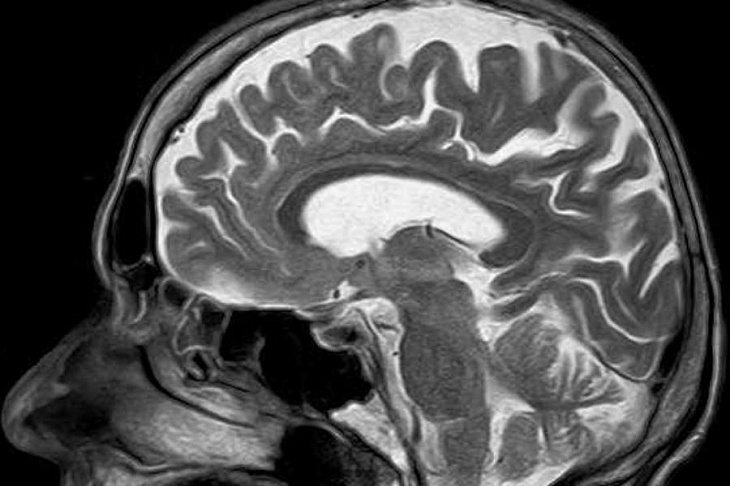

Medical Express рассказывает об уникальной системе - портативном сканере головного мозга. Известно, что стандартные МРТ-сканеры дороги, требуют специальной инфраструктуры и немобильны.

Группа исследователей из Массачусетской больницы общего профиля разработала недорогой, компактный, портативный и маломощный магнитно-резонансный томограф, который может быть установлен в машине скорой помощи, доставлен прямо в палату пациента или установлен в небольших клиниках и кабинетах врачей по всему миру.